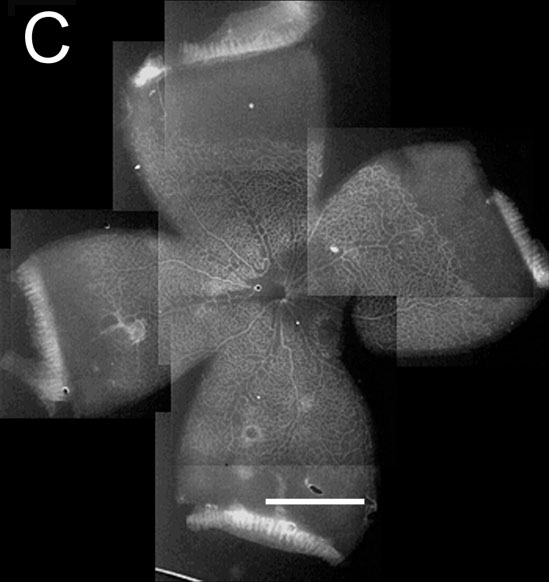

Figure 1. Lectin stained retinas from the room air control and 50/10 OIR groups

Blood vessels are white. A: P2 room air (RA) controls. B: P2 50/10 OIR model, 24 h of 50% oxygen followed by 24 h of 10% oxygen. The retinal vasculature is not only retarded but is also visibly less complex than the control (A). C: P7 RA controls. D: P7 50/10 OIR model after 3.5 cycles of 24 h of 50% oxygen, 24 h of 10% oxygen. The retinal vasculature is still delayed compared to the RA control (C). E: P14 RA control. The retina is fully vascularized and this is similar to the appearance of the RA control retina at P18. F: P14 50/10 OIR after 7 cycles of 24 h of 50% oxygen, 24 h of 10% oxygen. The retinal vasculature has covered about the same area as the P7 RA control (C) but appears much less dense. G: P18 experimental after 7 cycles of 24 h of 50% oxygen, 24 h of 10% oxygen and then 4 days in room air. This image of one of the quadrants shows the persistent avascular area (arrowhead) and tufts of endothelial cells (arrows) from intravitreous neovascularization. Scale bars represent 1.5 mm. See Table 1 for a quantification of avascular areas.